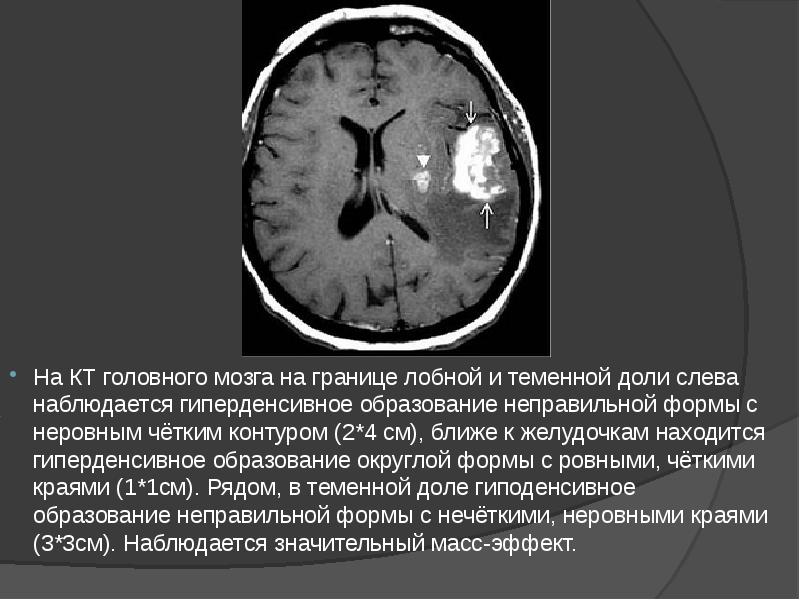

- 15. На КТ головного мозга на границе лобной и теменной доли слева